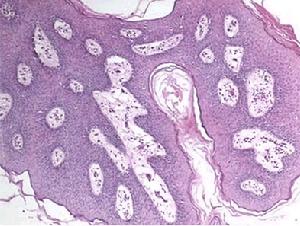

(2)局限型:多在胃竇部形成局限性膿腫,肉眼觀察,可見胃黏膜充血,可有糜爛,潰瘍,壞死及出血,顯微鏡下可見黏膜下層及肌層間質中血管充血,胃壁布滿纖維性網眼結構,其中含有膿液,並有大量白細胞浸潤。

本病的化膿過程可遍及全胃,但很少超過賁門或幽門,最常見於胃遠端的1/2。病變在胃黏膜下層。胃黏膜表面發紅,可有潰瘍、壞死、糜爛及出血。胃壁由於炎性腫脹而增厚變硬。切開胃壁可見有膿液流出。炎症可波及漿膜,甚至可出現胃壁穿孔。顯微鏡下可見黏膜下層有大量的白細胞浸潤,亦可看到多數細菌,有出血、壞死及血栓形成。肌層亦有白細胞浸潤。